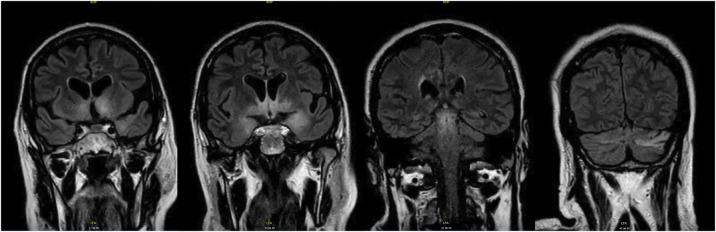

Results: A 72-year-old man presented with progressive hypersomnia and recurrent falls, initially misinterpreted as secondary to obstructive sleep apnea and cardiogenic syncope, respectively. Symptoms continued to worsen, prompting hospital admission. Video-polysomnography revealed a previously unreported sleep pattern, characterized by an abnormally increased proportion of REM sleep (approximately 3 times the expected), with sleep-onset REM periods occurring every time sleep was resumed after nocturnal awakenings. In addition, non-REM sleep was undifferentiated, without sleep spindles, K complexes, or slow-wave sleep. The recurrent SOREMPs raised suspicion of secondary narcolepsy. MRI showed T2 hyperintensities in different brain regions, including the hypothalamus, and CSF analysis confirmed anti-Ma2 antibodies and decreased hypocretin-1 levels. Symptoms only partially improved after immunotherapy, and malignancy screening remained inconclusive.